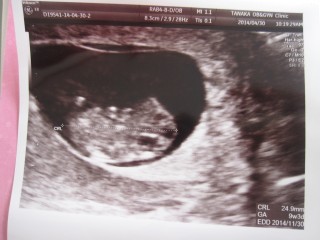

先生から元気に育ってるよ!の一言を 頂いきましたぁ(≧∇≦) 大きさは25mm♪♪ 次は二週間後。待ち長いなぁ~♡

手足が見えて旦那さんも大喜び。病院でかわいいと叫んでしまいました。ピピ大好き!